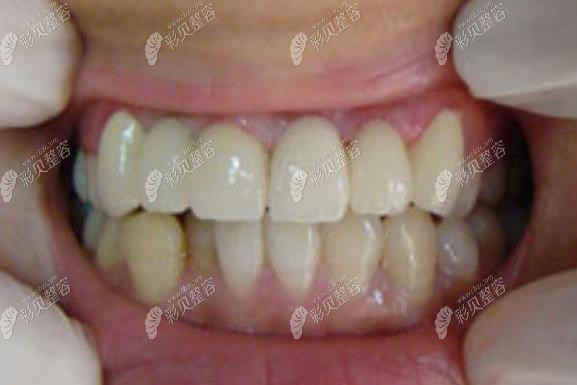

在朋友的安利下,我去宜昌中汉口腔诊所做了牙齿矫正,这是恢复后的效果图哟。

怎么样,对比术前照,术后是不是感觉上牙排整齐了不少,而且咬合也正常了呢?现在我朋友看见我都说跟换了个人一样,以前都没见过我开口笑的样子,而现在我好像每天都在笑。